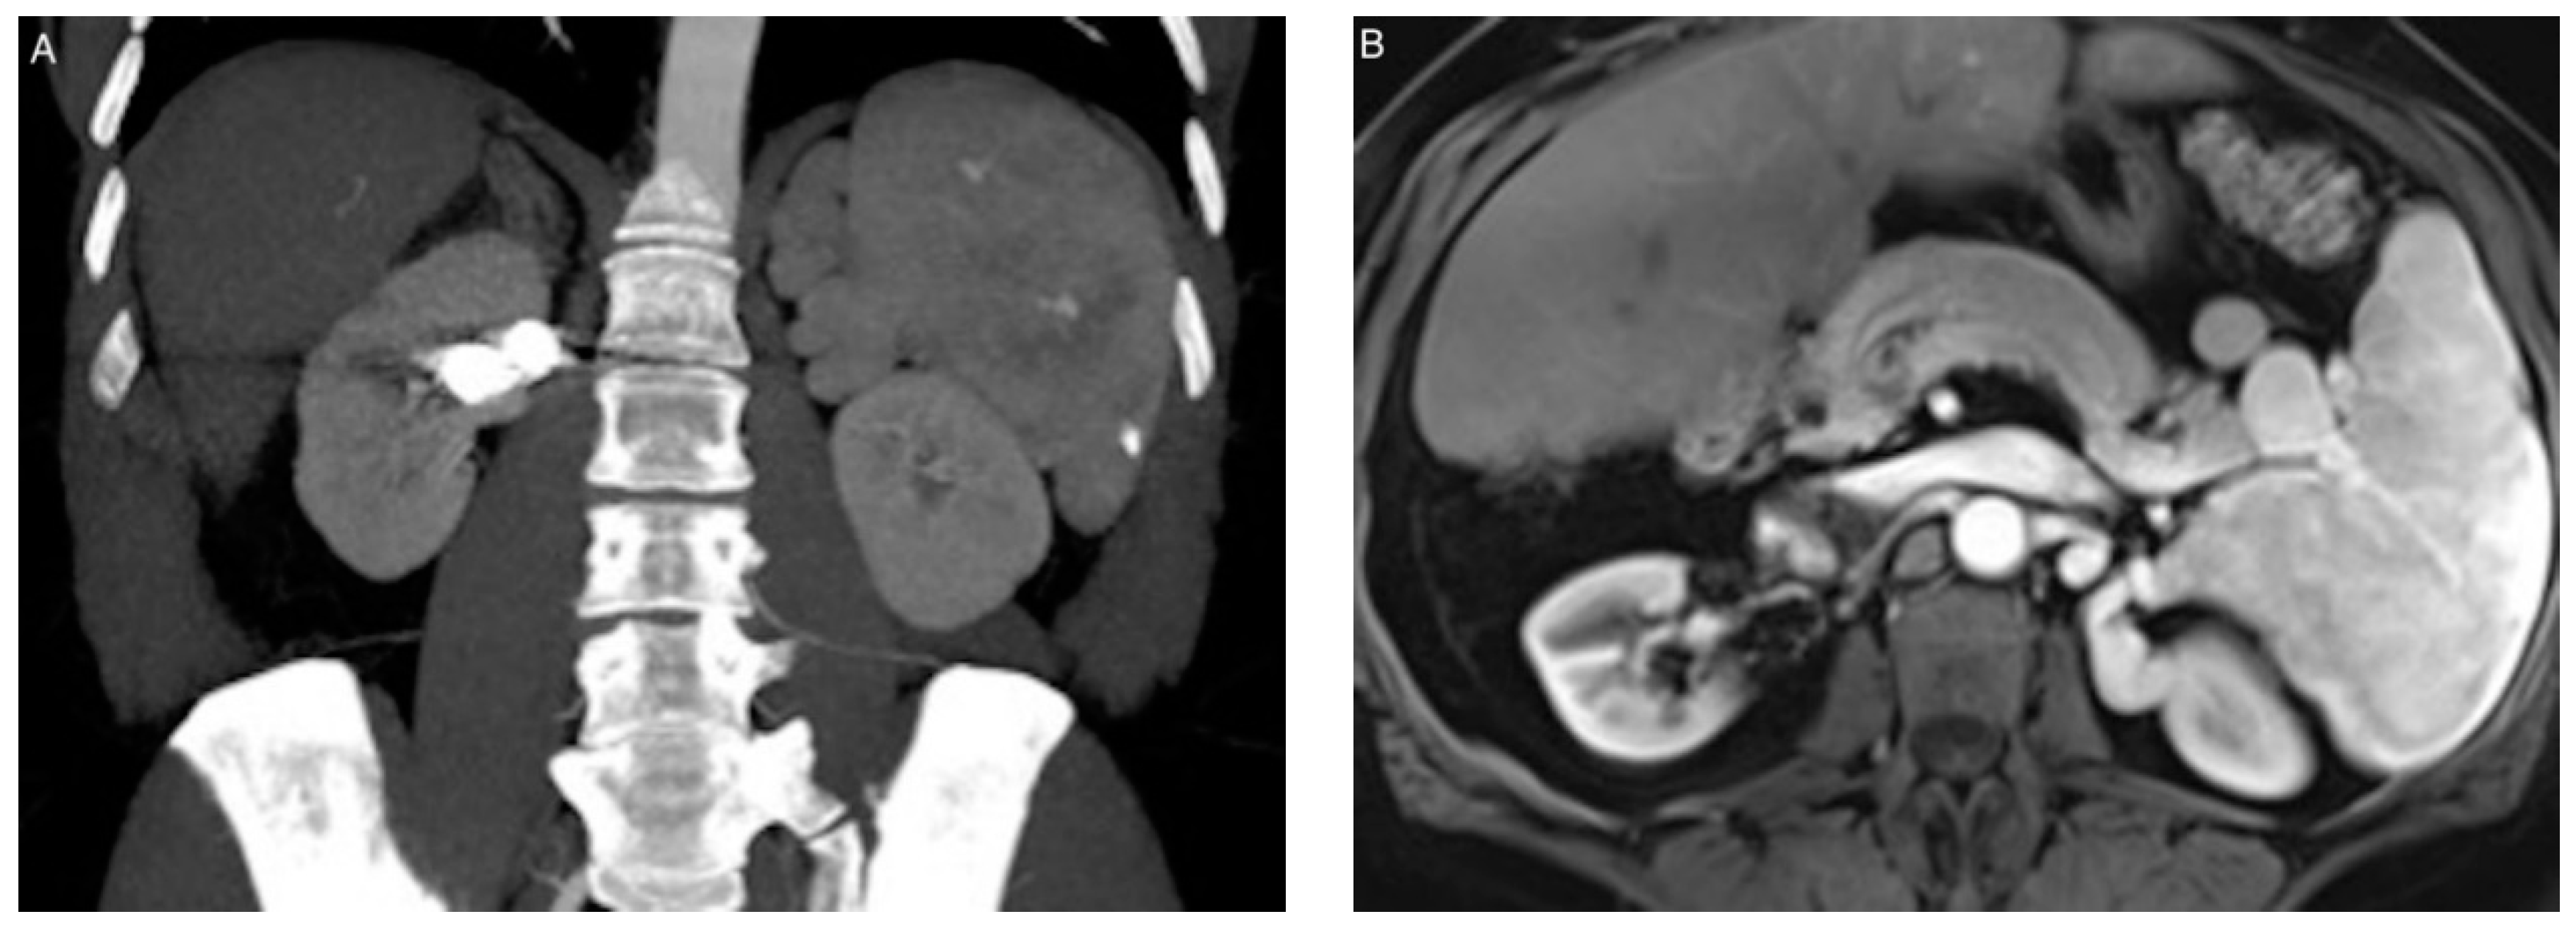

2.2. Endovascular Procedure

3.3. Coil Embolization and Outcomes

3.4. Complications

4. Discussion